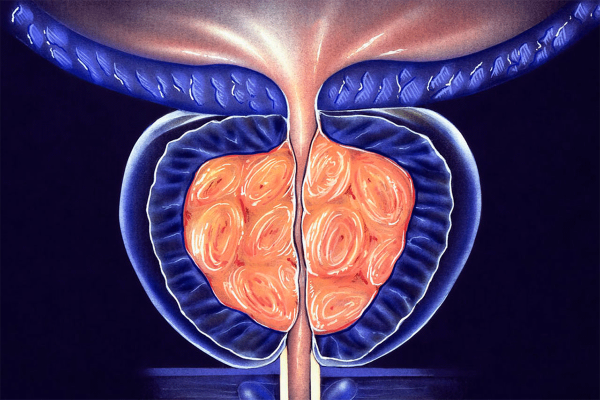

The most common prostate issue that men will be forced to reckon with (to some extent) is a condition known as benign prostatic hyperplasia (BPH).

BPH is a non-cancerous condition in which the prostate gland becomes enlarged. The prostate is a small gland located just below the bladder in men. As the prostate enlarges, it can press against the urethra (the tube that carries urine out of the body). This can cause urinary symptoms such as difficulty starting to urinate, a weak urine stream and the need to urinate frequently, especially at night.

The exact cause of BPH is unknown, but it is believed to be related to changes in hormone levels as men age. The prostate gland contains cells that respond to the male hormone testosterone. As men age, testosterone levels in their bodies decrease, but another hormone called dihydrotestosterone (DHT) levels remain the same. DHT causes prostate cells to grow and divide, leading to an enlarged prostate.

Symptoms of BPH and Other Issues

As stated previously, BPH is a condition that causes the prostate gland to become excessively enlarged. While this may seem trivial at face value, it’s a condition that can lead to many problems. The prostate is a small gland located below the bladder in men and as it enlarges, it can press against the urethra (the tube that carries urine out of the body) and cause urinary symptoms.

How the Prostate Works

The prostate gland is an organ located near the urethra in the male reproductive system. Its primary role is to produce and secrete a milky fluid known as prostate fluid. This fluid helps sexual health. The prostate also regulates urinary function, controlling urine flow from the bladder.

The prostate comprises two lobes, the anterior lobe, located in front of the rectum and the posterior lobe, which is located behind the prostate capsule. The prostate is surrounded by a muscular capsule and supported by a layer of connective tissue and fibrous ligaments. It is roughly the size of a walnut in adult men.

Several hormones, including testosterone and DHT, regulate the prostate. Testosterone is produced by the testes and is responsible for the development of male secondary sex characteristics such as facial and body hair and for regulating reproductive function. DHT is a testosterone metabolite accountable for prostate growth and size.

The prostate is composed of several different types of cells, including epithelial cells, which produce the prostate fluid and muscle cells. The prostate also contains a network of ducts, which transport prostate fluid into the urethra.

The prostate is under the control of testosterone and DHT. These hormones are responsible for the prostate gland’s development and maintenance. As men age, testosterone levels decrease, but DHT levels remain the same. This can cause prostate cells to grow and divide, leading to an enlarged prostate (BPH)